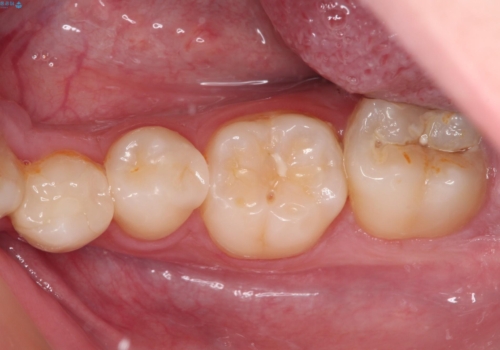

詰め物が欠けた セラミックインレーによる修復

- 以前治療した詰め物が欠けてしまったことを主訴として来院した患者様です。

食べ物がはさまったり、冷たいものがしみるといった症状がみられました。

むし歯の染め出し液と拡大鏡を用いて、むし歯がないことを確認し、

セラミックインレーにて修復することとしました。

食べ物がはさまりにくくなり、冷たいものがしみる症状もなくなり、大変満足していただきました。